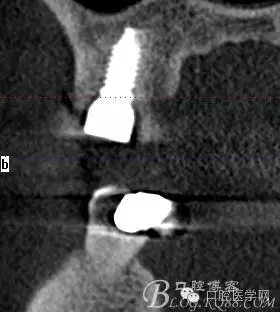

植入當然毫無難度可言,只是想術后的方向更加賞心悅目而已,14稍微有點難度,記住 上頜牙顎側(cè)骨板肯定比頰側(cè)硬多了。 所以(特別是柱行種植體柱行鉆)永遠要記住上頜牙備洞過程是會往頰側(cè)慢慢偏出去的 。(根型植體菱形鉆相對這個問題好控制點)所以我們第一鉆定位要比預計的中心點更加靠顎側(cè)多點 ,到底多多少,這個很難把握,感覺吧 。 上圖我畫了小圈的地方,是種植體離頰側(cè)和近中骨壁的距離空腔 (這個情況可以考慮植骨或者不植骨 我選擇了自體骨)。

軟組織簡單處理以后 簡單縫合 植體三維空間非常理想

術后片顯示方向非??梢?/p>

頰顎向的方向也很理想 箭頭所示 空間填滿了自體骨